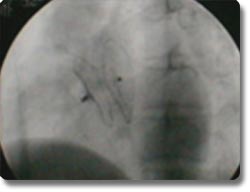

动脉导管未闭、房间隔缺损为先天性心脏发育缺陷,分别形成主动脉、肺动脉间及左右心房间的异常通道,传统治疗方式为外科开胸手术治疗。我科与国外同步开展了非手术经皮动脉导管封堵术及房间隔封堵术,用介入治疗方式矫正异常通道,手术时间30分钟左右,术后2天病员即可康复出院,疗效与外科开胸手术相同。 |